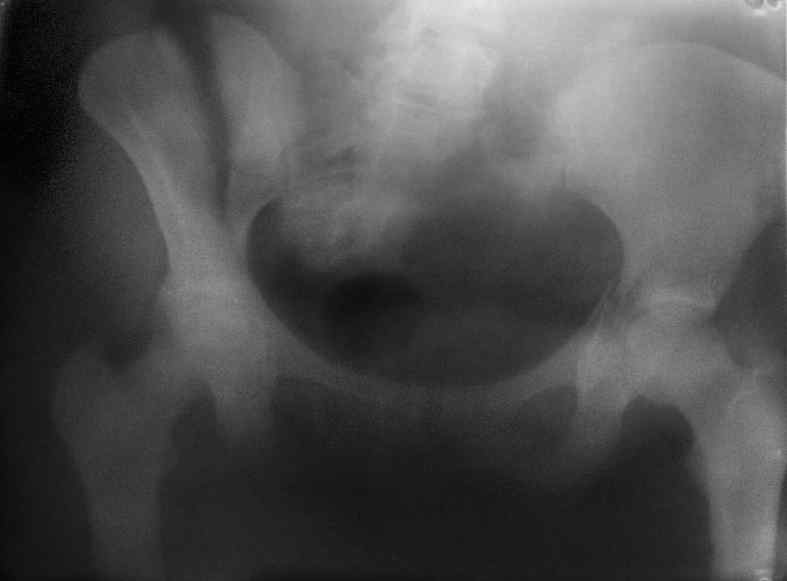

Молодая девушка 19 лет, травма 1 год назад, тогда же прооперирована.

В приложении снимки при поступлении и послеоперационные год назад.

Могу сказать одно: миграция винтов и нестабильность синтеза левого подвздошно-крестцовогоо сочленения очевидна.

Мы имели ввиду перелом крестца